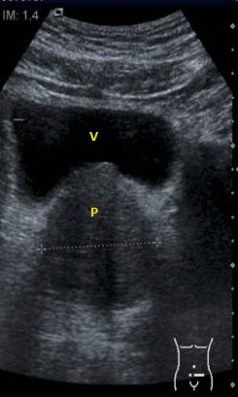

Quistes:

Los quistes se clasifican en:

1. Corticales.

2. Parapiélicos.

3. Sinusales.

Los quistes simples ecograficamente son anecoicos, presentan refuerzo posterior y su forma es redondeada u ovalada.

Los quistes complejos, contienen ecos en su interior, Presentan septos y calcificaciones.

Diferentes tipos de presentaciones quísticas.